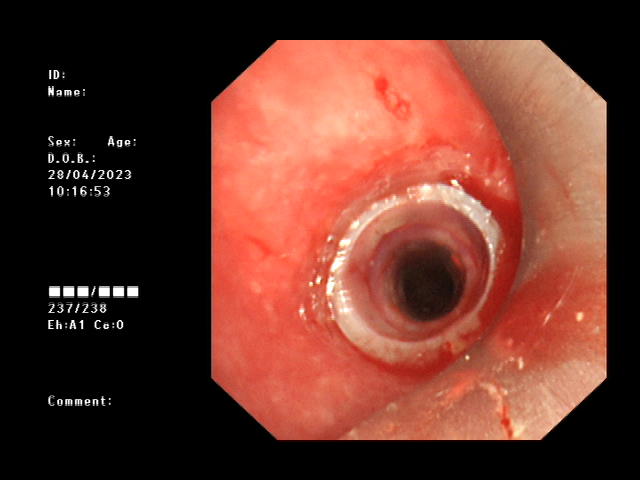

术前

经过术前的充分准备,患者在全麻下,用可弯曲支气管镜引导插入法插入硬镜,通过高频电刀放射状切开狭窄环,再予气道球囊扩张器扩张气道置入硅酮支架,并置入喉罩复苏,最后成功为患者实施硬质支气管镜技术。术后,患者气道通畅,无呼吸困难、气促等症状出现,对比术前生活质量得到明显改善。

高频电刀切开狭窄环